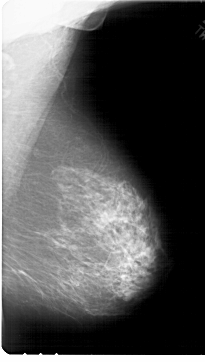

A_1789_1.RIGHT_MLO

RIGHT_MLO LINES 6871 PIXELS_PER_LINE 3886 BITS_PER_PIXEL 12 RESOLUTION 43.5 NON_OVERLAY